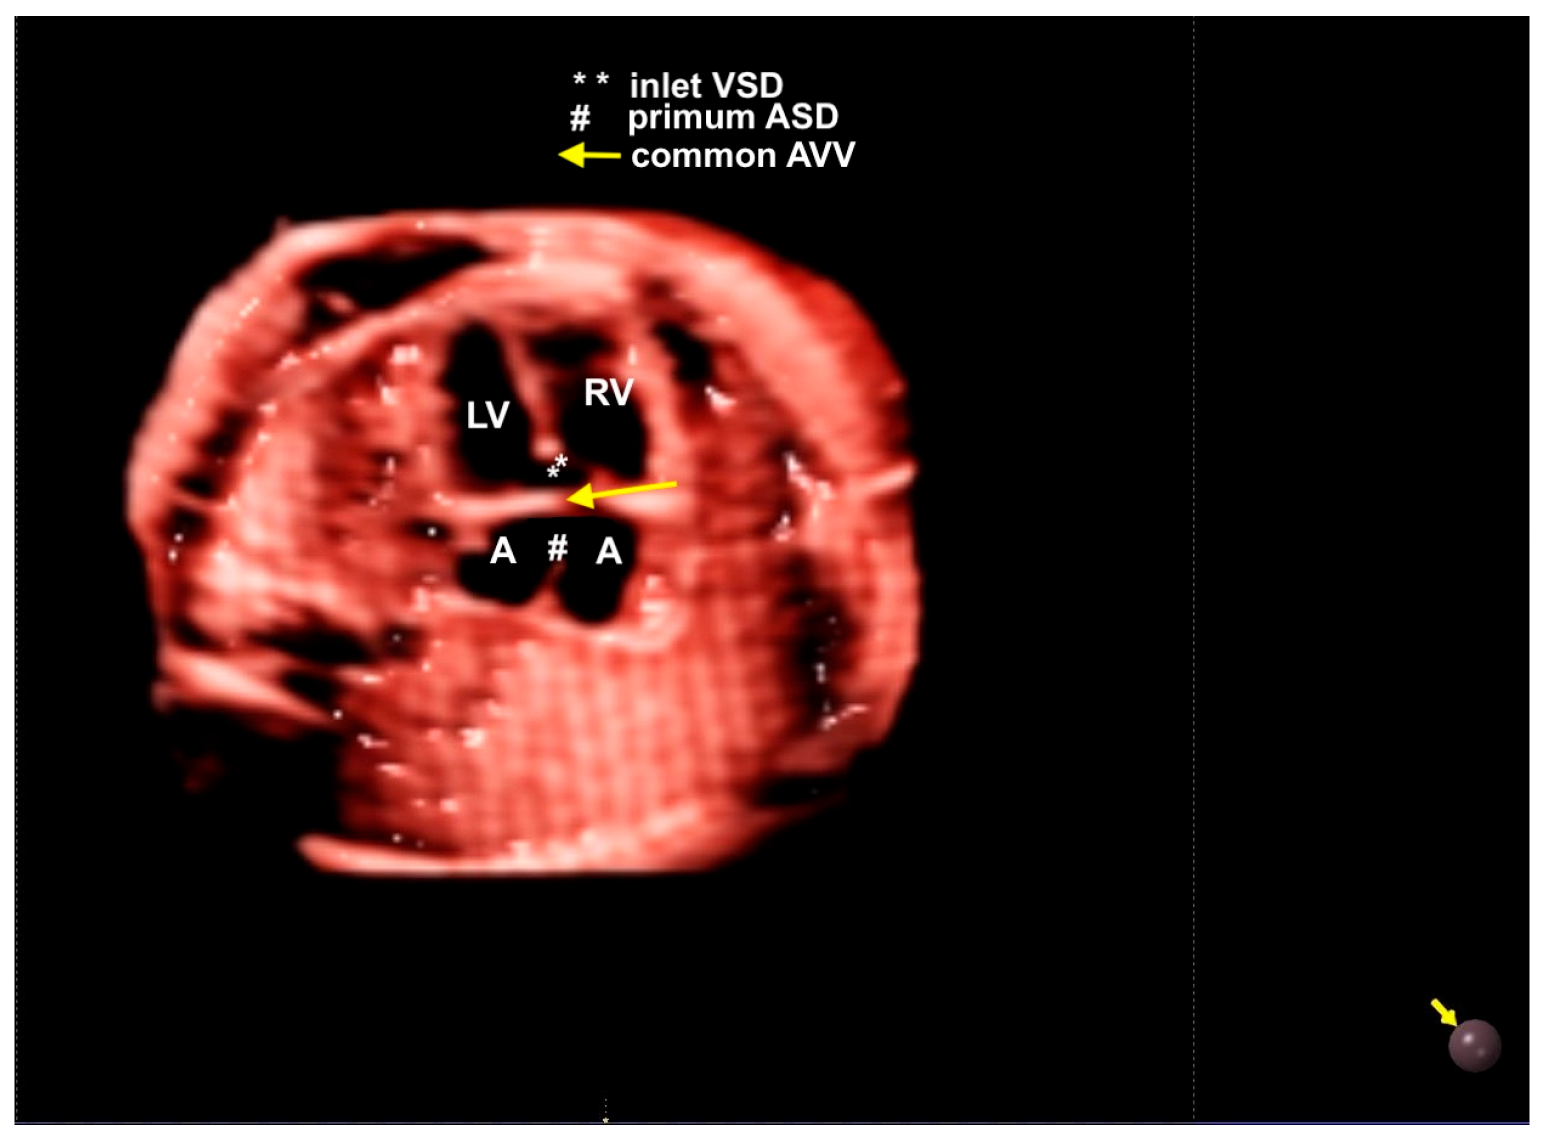

8. Atrioventricular Septal Defect

- Veronese, P.; Guariento, A.; Cattapan, C.; Fedrigo, M.; Gervasi, M.T.; Angelini, A.; Riva, A.; Vida, V. Prenatal Diagnosis and Fetopsy Validation of Complete Atrioventricular Septal Defects Using the Fetal Intelligent Navigation Echocardiography Method. Diagnostics 2023, 13, 456. [Google Scholar] [CrossRef]